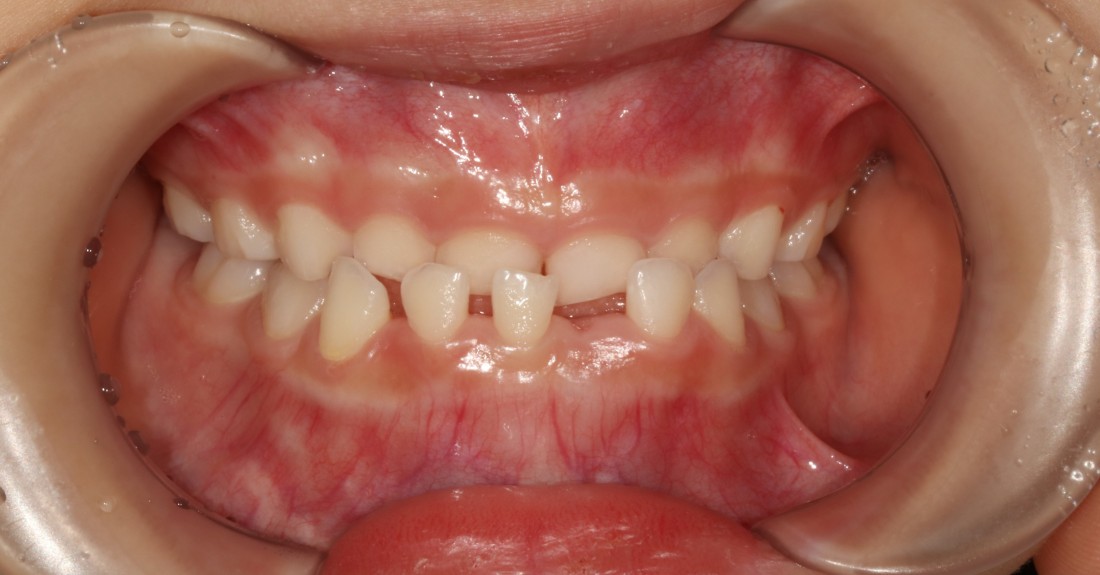

혹시 우리아이 치아가

이렇게 윗니보다 아랫니가 앞으로 나오며

맞물리고 있는 반대교합처럼 보이시나요?